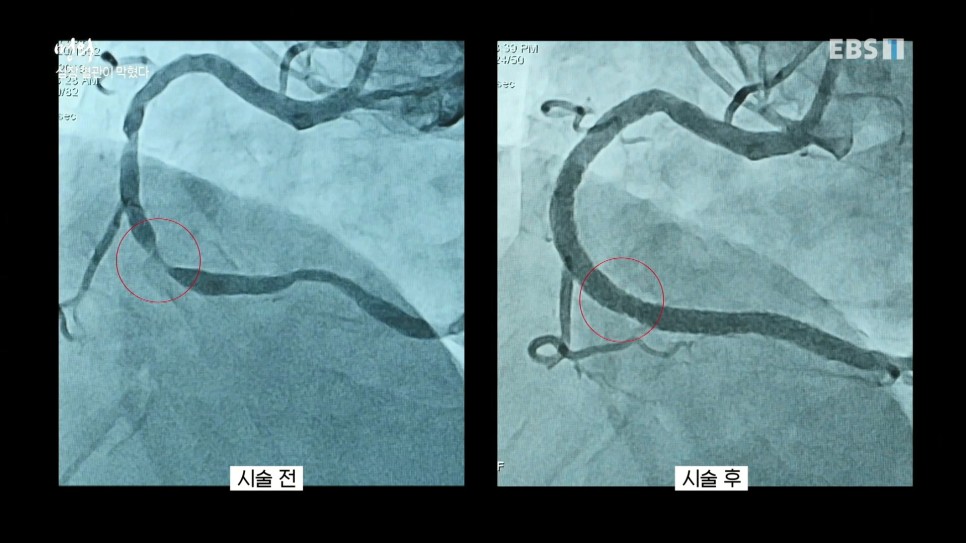

협심증이나 심근경색증은 환자의 사타구니 혈관에 철사처럼 가느다란 카테터를 넣어 막힌 심장쪽 혈관에 접근하여 혈관이 막힌 부분에 정확히 도달하면 그물망 모양의 스텐트를 넣어 벌리고 스텐트가 넓어져 좁았던 혈관이 넓어집니다. 시술 전 끊어진 것처럼 보이던 혈관이 시술 후 굵고 선명하게 보이는 것은 계획대로 수술이 잘 이뤄진 표시입니다.